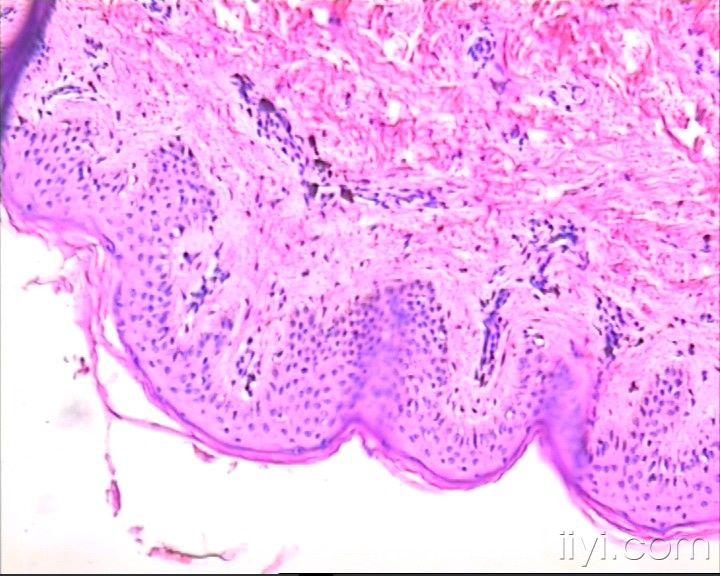

全身皮肤色斑——色素性玫瑰疹

患者女,12岁,2010年1月从腹部皮肤开始出现鲜红色皮肤斑块,伴瘙痒,逐渐蔓延至全身皮肤(面部,手、足除外)。2010年3月开始,皮肤斑块转为褐色。病检取自背部皮肤。患者肝肾功及血常规均正常,无其它异常表现,目前皮损无瘙痒。

我们最终考虑为色素性玫瑰疹。